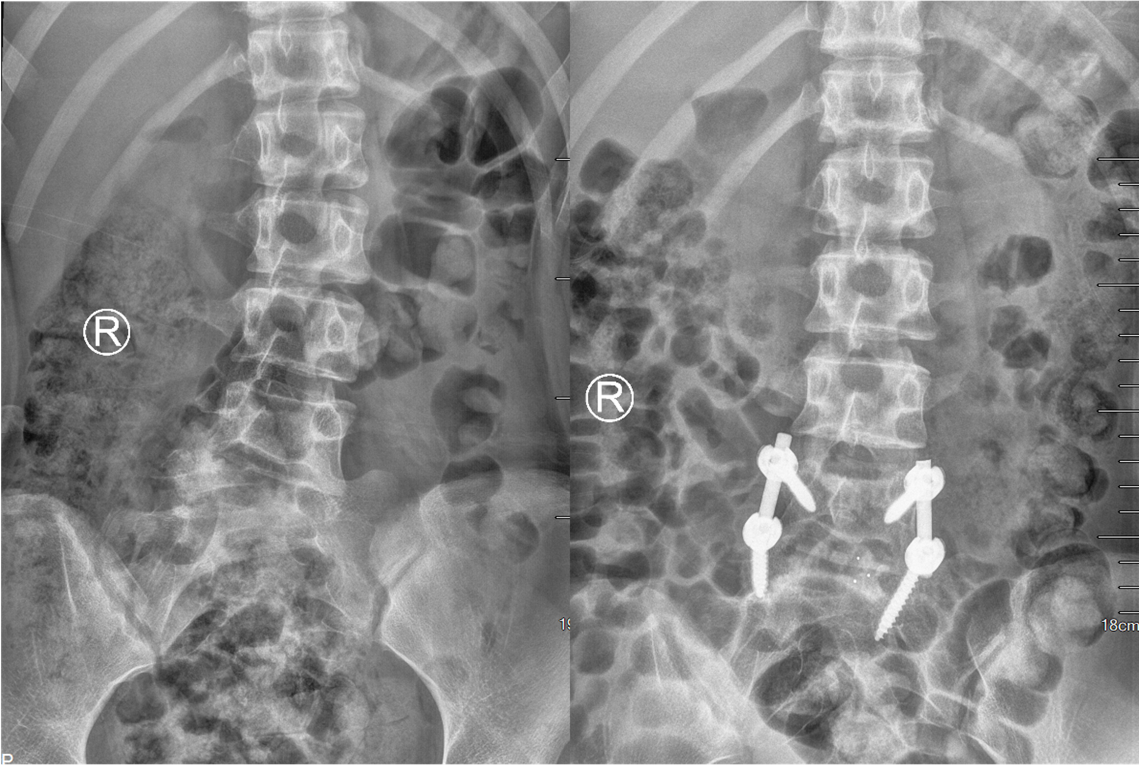

姜主任为小姑娘做了详细的体格检查,仔细阅读了影像资料后告知小王的父亲,孩子患的是一种第5腰椎先天性半椎体畸形而导致的腰椎侧弯畸形,采取手术方式干预迫在眉睫,否则畸形将会进一步加重。患者家属之前听说这种矫形手术切口很大,还需要打上十几个钉子,一直十分犹豫。看着患者父亲那焦急的神情,姜主任笑着安慰道:我们只需要采用相对小的手术把半椎体切除,再做适当的矫形即可。其余的部分畸形会随着生长发育自行矫正。在姜主任的耐心解释下,家属悬着的心终于放了下来,办理住院登记手续后不久顺利入院骨科病房。

入院进一步完善各项检查后,姜为民主任再一次对小王的影像资料进行了全面的研究,同时与团队成员商讨制定详细的手术方案。计划首先经后路切除L5半椎体,然后行椎间盘摘除凹侧椎间隙撑开矫形,再置入融合器行椎间融合,最后行短节段椎弓根内固定,以尽可能小的代价取得较为理想的效果。手术当日,姜主任熟练的通过截骨、置钉、撑开矫形、植骨融合等操作,顺利完成了手术。术后,患者小王恢复良好,术后影像检查显示半椎体已完全切除,矫形效果满意,手术非常成功。